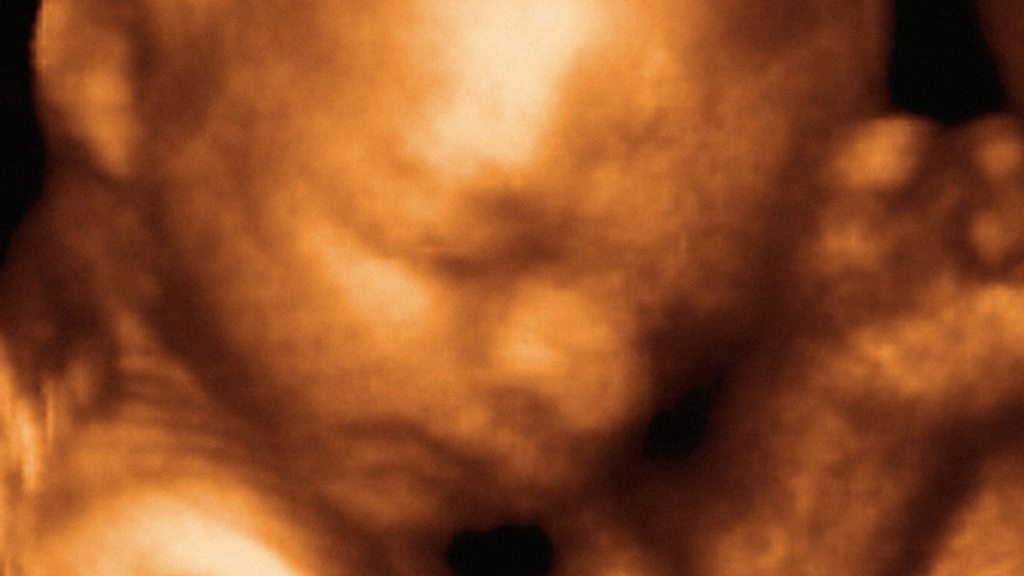

On the 10th May 1981 a baby was born after having been successfully operated on whilst still in the womb. The paediatric surgeon who developed the technique was Dr Michael Harrison. He has been speaking to Ashley Byrne about the challenges he faced. Photo: an ultrasound of a foetus in the womb. Credit: Science Photo Library.